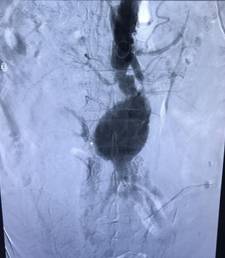

经历了一天一夜值班未眠,凌晨5点27分神经内科急诊手术还在持续进行中,急诊电话又一次响起,周围血管科一例腹主动脉瘤合并严重冠心病患者,一旦腹主动脉瘤破裂,就会造成大出血、失血性休克等,从而危及患者生命,现需要立即行急诊腹主动脉瘤腔内隔绝术。胡新华老师立即再次启动备班护士,准备急诊手术用物及急救配合用物,田红燕主任及张军波教授很快也已就位,随后病人入室顺利开始手术。就在手术刚开始进行时,患者突然出现面色苍白,大汗淋漓,再次腹痛且加剧,血压骤降至60/40mmHg,心率加快至130次/分,在田主任与张教授指挥下,胡新华老师与备班护士霍达紧急进行抢救,她们反应迅速,处理果断,默契配合田红燕主任与张军波教授紧急行球囊阻断腹主动脉,快速植入覆膜支架,很快病人腹痛减轻生命体征恢复平稳,转危为安,手术顺利结束,患者安全出室返回病房。

手术结束后,胡新华老师和护士霍达都受到田红燕主任及张军波教授的高度赞扬,在这生死时刻,腹主动脉瘤术中破裂死亡率高达90%以上的情况下,能将病人从死亡线上拉了回来,离不开室内护士的密切配合和护士在工作中所拥有的过硬急救技能及应变能力。当田主任和张军波教授以及胡新华老师和霍达护士安全将病人送出介入手术室时都已是第二天早上八点了,虽然在这紧张的24小时内,但能与死神赛跑,把病情如此危重的患者从生死边缘拉回来,值了!